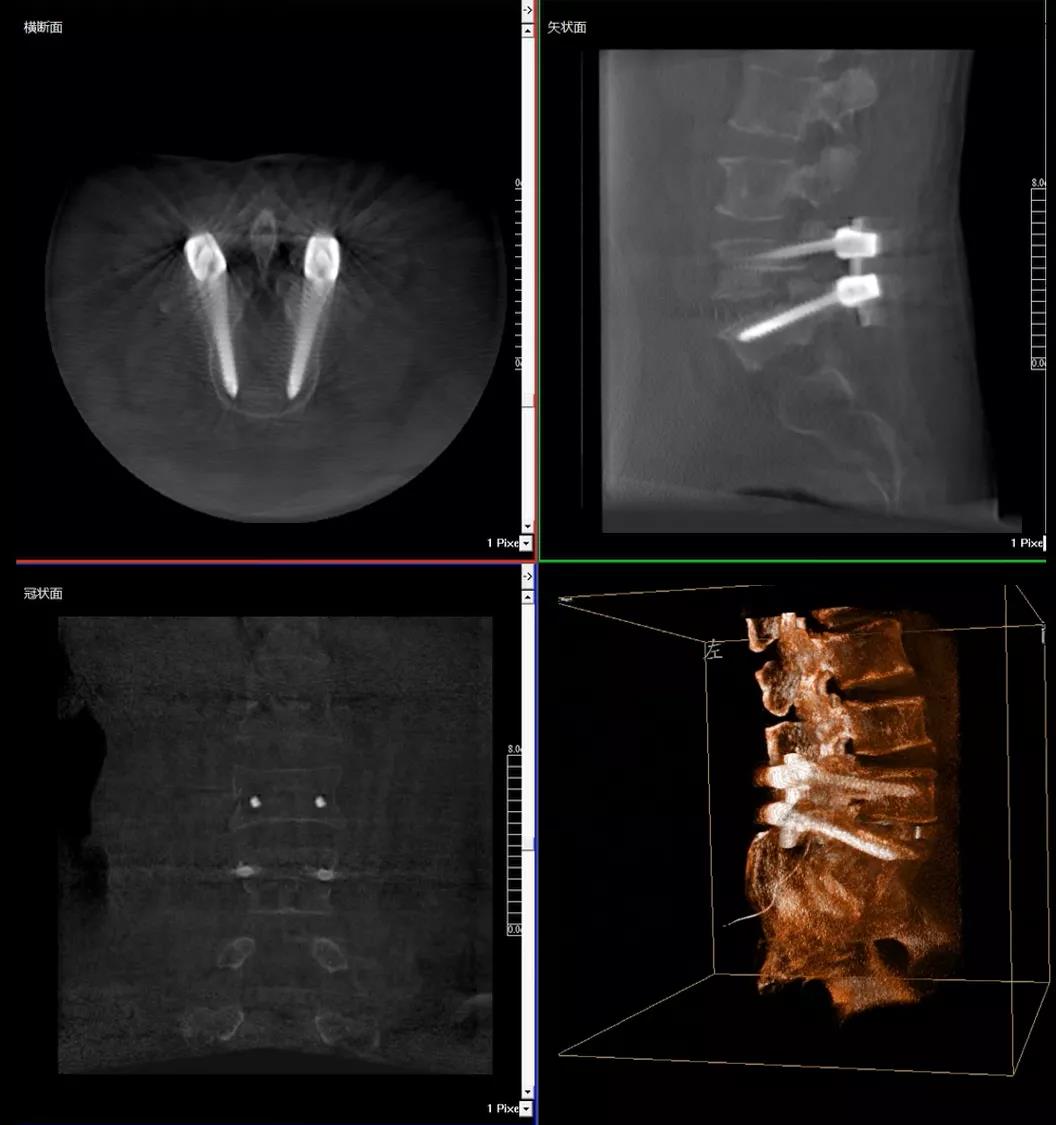

患者1:女性,56歲,L5/S1椎間盤椎板減壓+釘棒固定術(shù)

醫(yī)生在影像引導(dǎo)下在L5/S1椎弓根處打入醫(yī)用螺釘

術(shù)中快速生成橫斷面、矢狀面、冠狀面斷層圖像和三維立體圖像